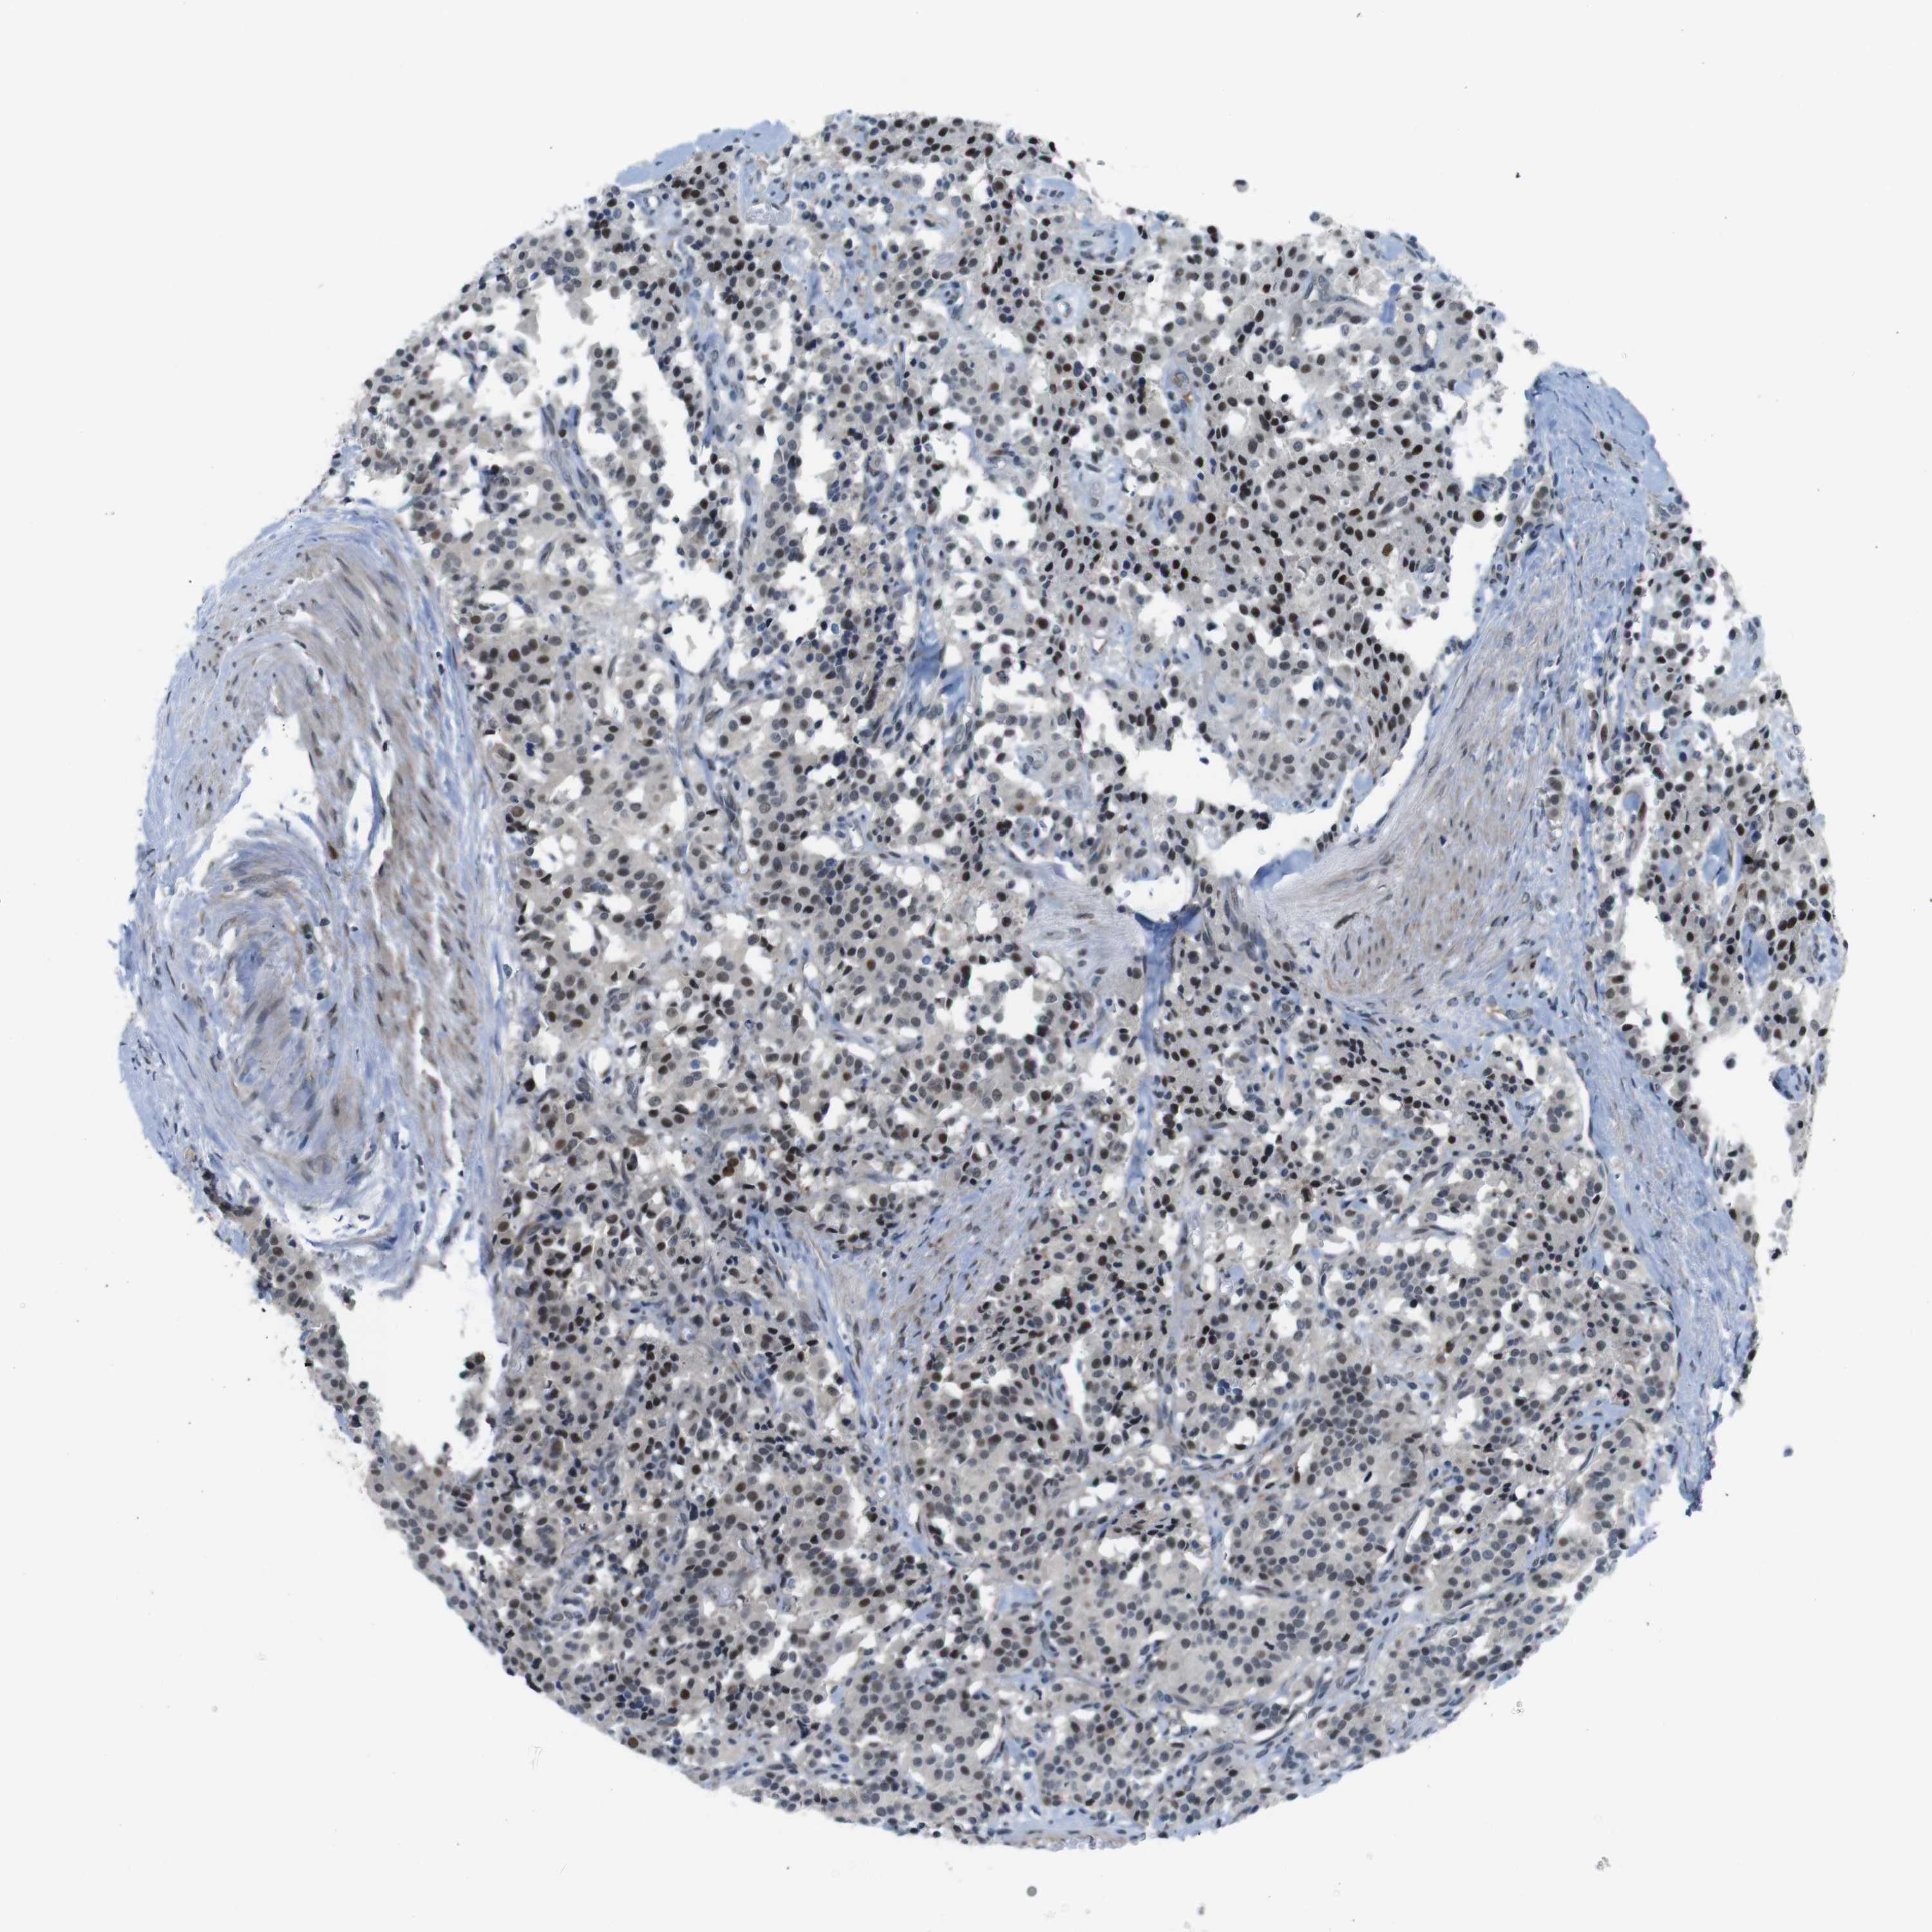

CARCINOID - Protein expressioni

A mouse-over function shows sample information and annotation data. Click on an image to view it in a full screen mode. Samples can be filtered based on level of antibody staining by selecting one or several of the following categories: high, medium, low and not detected. The assay and annotation is described here.

Antibody stainingi

Antibody staining in the annotated cell types in the current human tissue is reported as not detected, low, medium, or high, based on conventional immunohistochemistry profiling in selected tissues. This score is based on the combination of the staining intensity and fraction of stained cells.

Each image is clickable and will lead to virtual microscopy that enables deeper exploration of all samples and also displays staining intensity scores, fraction scores and subcellular localization as well as patient and tissue information for each sample.

Antibody HPA014366

Staining

High

Medium

Low

Not detected

Intensity

Strong

Moderate

Weak

Negative

Quantity

>75%

75%-25%

<25%

None

Location

Nuclear

Cytoplasmic/membranous

Cytoplasmic/membranous,nuclear

Carcinoid, malignant, NOS

Carcinoma, NOS